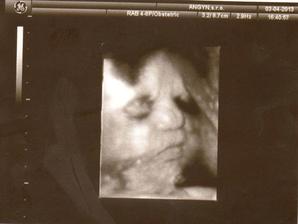

3.4.2013 - 31tt. návšteva poradne, USG, 1779 gramov, 3D úspešné, smiala sa a vyplazovala jazyk